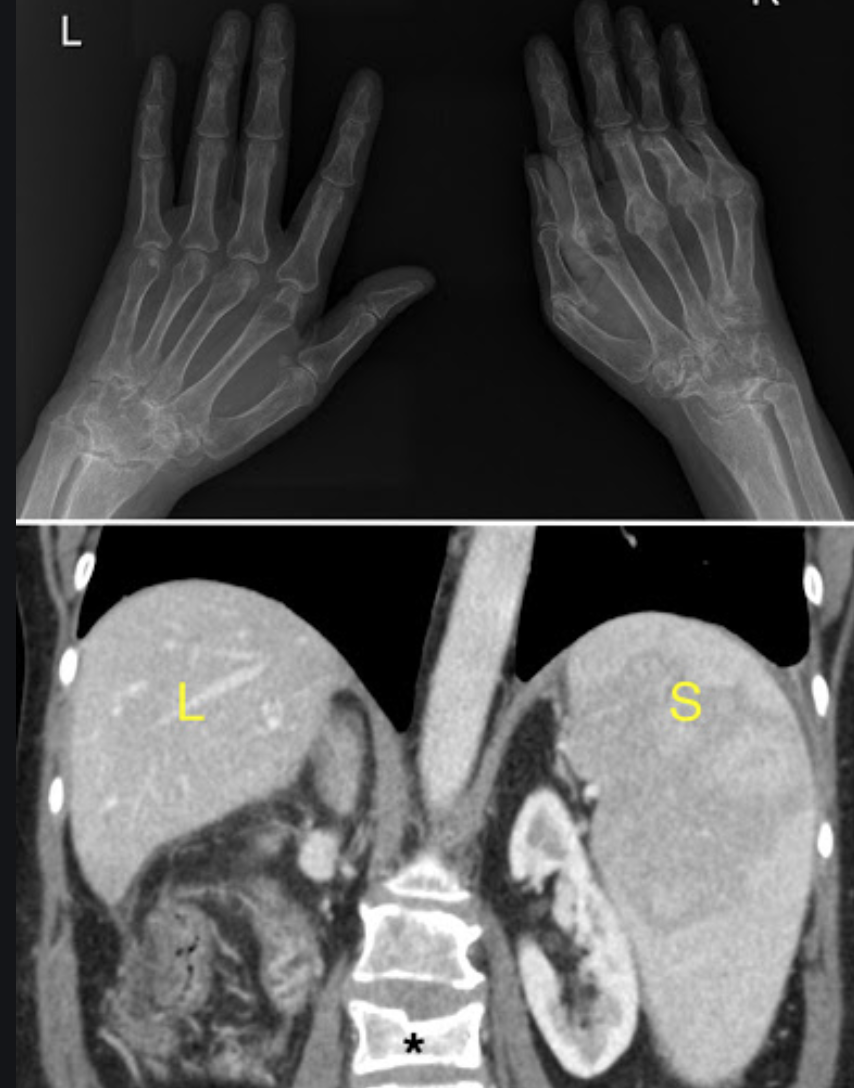

Felty syndrome

Assoc Prof Craig Hacking◉◈ and Dr Yuranga Weerakkody◉ et al.

Felty syndrome is a rare haematological syndrome in rheumatoid arthritis.

Felty syndrome comprises of the triad of:

rheumatoid arthritis

typically with severe articular and extra-articular disease

splenomegaly

neutropenia

Additionally, patients may have bicytopaenia or pancytopaenia, recurrent bacterial infections, and non-cirrhotic portal hypertension.